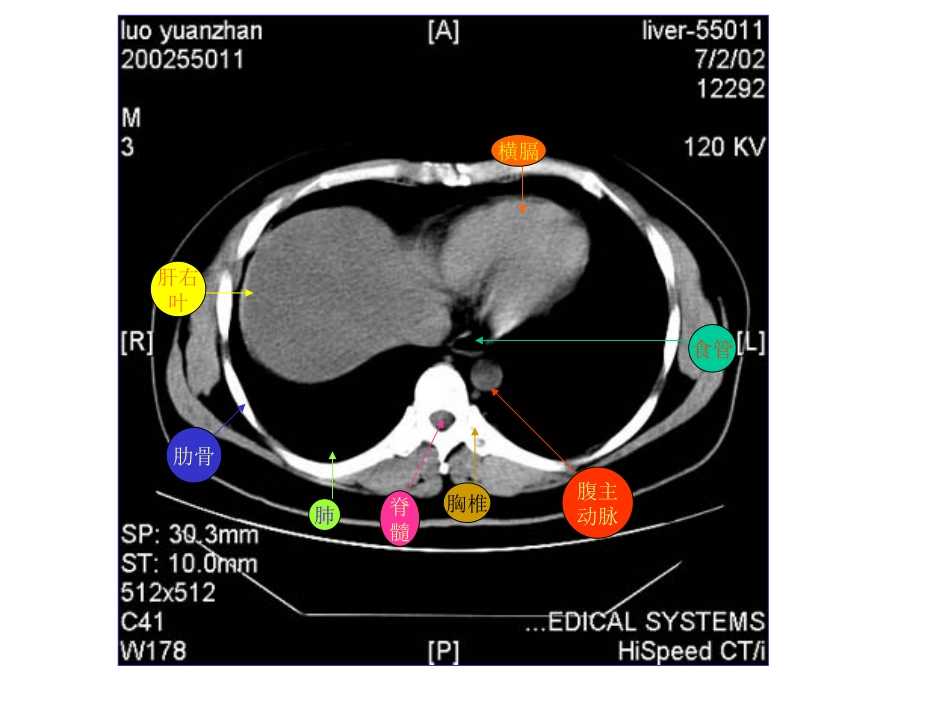

肝右叶横膈肺胸椎脊髓腹主动脉食管肋骨肋骨肝右叶腹主动脉食管肺肝左叶肝右叶腹主动脉胃脾肝尾叶肝右叶尾叶膈脚脾门静脉肝左叶胃肝右叶膈脚腹主动脉脾胆囊胃肝右叶下腔静脉胰腺脾胃腹主动脉肝右叶心脏腹主动脉下腔静脉脊髓食管肺肝左叶肝右叶腹主动脉下腔静脉胃脾脊髓肝左叶及肝左动脉肝右叶及肝右动脉腹主动脉下腔静脉胃脾肝尾叶肝右叶下腔静脉腹主动脉胃脾膈脚肝静脉下腔静脉腹主动脉食道肝右叶下腔静脉肝右叶肝静脉肝左叶腹主动脉胃脾肝尾叶肝右叶下腔静脉腹主动脉门静脉主干肝左叶胃脾肝右叶下腔静脉门静脉腹主动脉膈脚脾胃肝血管瘤CT平扫呈低密度灶,密度均匀,边缘较清。肝血管瘤静脉注入造影剂后CT扫描,动脉期示:病灶由边缘向中心结节状强化,逐渐填满,其密度与同层腹主动脉相似。腹主动脉肾肝血管瘤静脉期示病灶进一步强化填充,呈密度较均的高密度灶,显示更清楚。肝血管瘤2分钟后,平衡期CT扫描示病灶仍呈较高密度,显示清楚,表现为“早出晚归”征肝血管瘤CT平扫示肝脏左右叶普遍增大。静脉注入造影剂后CT扫描,静脉期示肝实质呈不均匀强化。门静脉肝硬化:CT平扫示肝脏左右叶体积缩小,边缘欠平整,肝裂增宽肝裂增宽肝硬化并门静脉高压,静脉注入造影剂后静脉期CT扫描示:脾门静脉曲张。脾门静脉曲张脾肝右叶肝左叶肝癌CT平扫示:肝脏体积明显增大,边缘不平整,肝实质密度不均,内见结节状、团块状低密度癌灶,边缘模糊,密度不均。肝右叶巨大癌灶肝内结节状癌灶静脉注入造影剂后CT扫描,动脉期示:肝内癌灶不均匀增强,密度增高,其内见肿瘤坏死部分不强化,呈更低密度。癌灶增强,密度增高瘤内坏死部分呈更低密度静脉早显肿瘤血管肿瘤假包膜静脉注入造影剂后CT扫描,静脉期示下腔静脉内癌栓呈低密度充盈缺损表现。肝右叶癌灶腹主动脉静脉注入造影剂后CT扫描,静脉期示:由于造影剂洗脱,肿瘤呈较低密度。本例见癌肿侵犯门静脉,门脉左支受压变形,门脉右支未见显影。门静脉左支受压变形肝内癌灶静脉注入造影剂后CT扫描,平衡期示:肝内癌灶随造影剂进一步洗脱呈低密度表现。本例门静脉左支内还可见稍低密度癌栓。门静脉左支及其内癌栓肝内癌灶胆囊体积缩小,胆囊壁稍厚。肾胰肝肾静脉腹主动脉慢性胆囊炎CT平扫示:胆囊体积缩小,胆囊后壁见一类椭圆形高密度结石胆囊结石腹水肝胰肠管脾腹水肾正常胰腺CT平扫胰腺体、尾部胆囊肝右叶脾肠管下腔静脉膈脚腹主动脉正常胰腺CT平扫肝右叶胰头肠管肾腹主动脉下腔静脉静脉注入造影剂后,正常胰腺CT对比增强扫描胆囊肝右叶下腔静脉胰体胰尾脾肾肠管脾静脉静脉注入造影剂后,正常胰腺CT对比增强扫描胰头下腔静脉肝右叶腹主动脉肾肠管脾静脉脾急性单纯性胰腺炎CT平扫胰腺肝脾左肾下腔静脉腹主动脉胃急性单纯性胰腺炎CT平扫胰腺脾右肾肝下腔静脉腹主动脉胆囊胃急性单纯性胰腺炎CT平扫胰头胃肝胆囊脾左肾下腔静脉腹主动脉肠管急性单纯性胰腺炎CT对比增强扫描胰腺胃胆囊肝下腔静脉腹主动脉脾静脉左肾脾急性单纯性胰腺炎CT对比增强扫描腹主动脉脾静脉下腔静脉胰头肝胆囊胃左肾脾肠管急性渗出性胰腺炎CT平扫胰腺胃肝脾右肾下腔静脉腹主动脉急性渗出性胰腺炎CT平扫胰腺胃肝脾腹主动脉下腔静脉右肾肾前筋膜增厚胆囊急性渗出性胰腺炎CT平扫胰腺胃胆囊肝右肾下腔静脉腹主动脉肾前筋膜增厚左肾脾慢性胰腺炎CT增强扫描示:胰管扩张胰腺扩张胰管胃胆囊增大肝右肾右肾静脉腹主动脉左肾左肾静脉脾胰腺体积缩小胰腺胃脾左肾肝右叶肝左叶下腔静脉腹主动脉